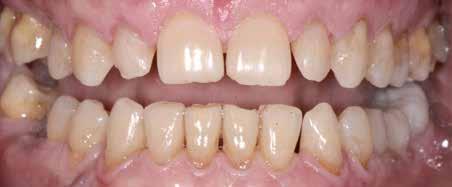

A felnőtt páciensek kezelése során általában egyszerre több ellátásra szoruló elváltozást is diagnosztizálhatunk: hiányzó fogak, kopott fogazat, esetleg régi, nem megfelelő, sérült fogpótlások, rendellenes helyzetben lévő fogak stb… Ezen páciensek kezelésekkel kapcsolatos kérései mindig az esztétikai vagy a rágással kapcsolatos kívánságaik kielégítését szolgálja. A kezelések során a fogorvosoknak nem csak a páciensek kéréseinek teljesítésére, hanem ezzel egyidejűleg a fogazat általános megjelenésének és funkciójának lehetőség szerinti javítására is törekedniük kell. Mindemellett a lehető legtöbb saját foganyag megőrzését és az évek során elvesztett kemény- és lágyrészek pótlását (pl.: hiányzó fogak, sorvadt állcsontgerinc, lágyszöveti defektusok) is szem előtt kell tartaniuk, úgy, hogy közben egy hosszú távon fenntartható eredményekkel járó kezelési tervet állítanak össze. Ezek mindig összetett esetek. Annak érdekében, hogy a fentiekben megfogalmazott összes kezelési célt teljesíteni tudjuk, interdiszciplináris megközelítésre van szükség. Az ilyen komplex rehabilitációs kezeléseket „fogászati megfiatalításnak” nevezzük. Ezeknek a beavatkozásoknak lényege az elhasználódott fogazat biológiai szempontokat figyelembe vevő minimál invazív módon történő helyreállításában rejlik, mely folyamat végére a páciensek fogai visszanyerhetik fiatalkori megjelenésüket.

A rehabilitációs kezeléseknek a célja, hogy a páciensek a lehető leghosszabb időn keresztül képesek legyenek mosolyogni és rágni. A protetikai kezeléseket végző fogorvosoknak helyre kell tudni állítaniuk a fogívek szabályos lefutását és az alsó és felső fogív között megfelelő interokkluzális érintkezéseket kell létrehozniuk. Így lehet csak az ellátás befejezését követően elért végeredmény biológiai szempontokat figyelembe vevő esztétikáját, funkcionális megfelelőségét, hosszú távú fenntarthatóságát biztosítani.

Nagyon fontos, hogy már a kezelések elején meghatározzuk, hogy melyek azok a hiányzó fogak, amelyeket a későbbiekben pótolni szeretnénk, valamint helyesen diagnosztizáljuk a kariológiai, endodonciai vagy parodontológiai okok miatt ellátást igénylő elváltozásokat. Szintén kiemelt jelentőséggel bír a fogak megtarthatóságának kiértékelése. A kezelési terv felállítása során tisztában kell lennünk azzal, hogy mely fogak alkalmasak fogpótlások ideiglenes vagy végleges elhorgonyzására.

A preprotetikai fázisban el kell látnunk a diagnosztizálásra került kórfolyamatokat, megfelelő pozícióba kell állítanunk a megtartani kívánt fogakat, pótolnunk kell az elvesztett csontállományt, valamint gondoskodnunk kell az íny megfelelő állapotáról. Ha szükség van rá, úgy a foghiányok pótlására szolgáló dentális implantátumok is ebben a fázisban kerülnek behelyezésre. Általánosságban elmondható, hogy azokat a kezeléseket, amelyek befejezése biológiai okok miatt hosszú időt vesz igénybe (pl.: fogszabályozás, csontpótlás, implantáció), a lehető leghamarabb érdemes elkezdeni.

A fogszabályzó kezelések egyik legfontosabb célja, hogy elérjük a lehető legharmonikusabb interokkluzális fogérintkezéseket, továbbá az állcsont relációs helyzetének frontális és szaggitális síkban is megfelelőnek kell lennie. A fogszabályzás befejezésekor a fogpozícióknak nem orthodonciai, hanem protetikai szempontok szerint kell ideálisnak lenniük. Az Invisalign ClinCheck szoftver (Align Technology) segítségével a protetikus az orthodontussal együtt meg tudja határozni azokat a végső fogpozíciókat, amelyek a lehető legjobb végeredmény biztosításához elengedhetetlenek. Bizonyos klinikai paramétereket, mint a fogak klinikai koronájának nagyságát, az egyes fogak fogíven belüli optimális pozícióját, a fogívek egymáshoz viszonyított helyzetét, a fogak között látható rések nagyságát, a frontfogak tengelyének dőlését, az overjet és overbite mértékét már a kezelések megkezdése előtt pontosan definiálni kell. Ezeket az adatokat viszont csak a tervezett végleges fogpótlás ismeretében lehet meghatározni, ezért van szükség az orthodontus és a protetikus szoros együttműködésére.